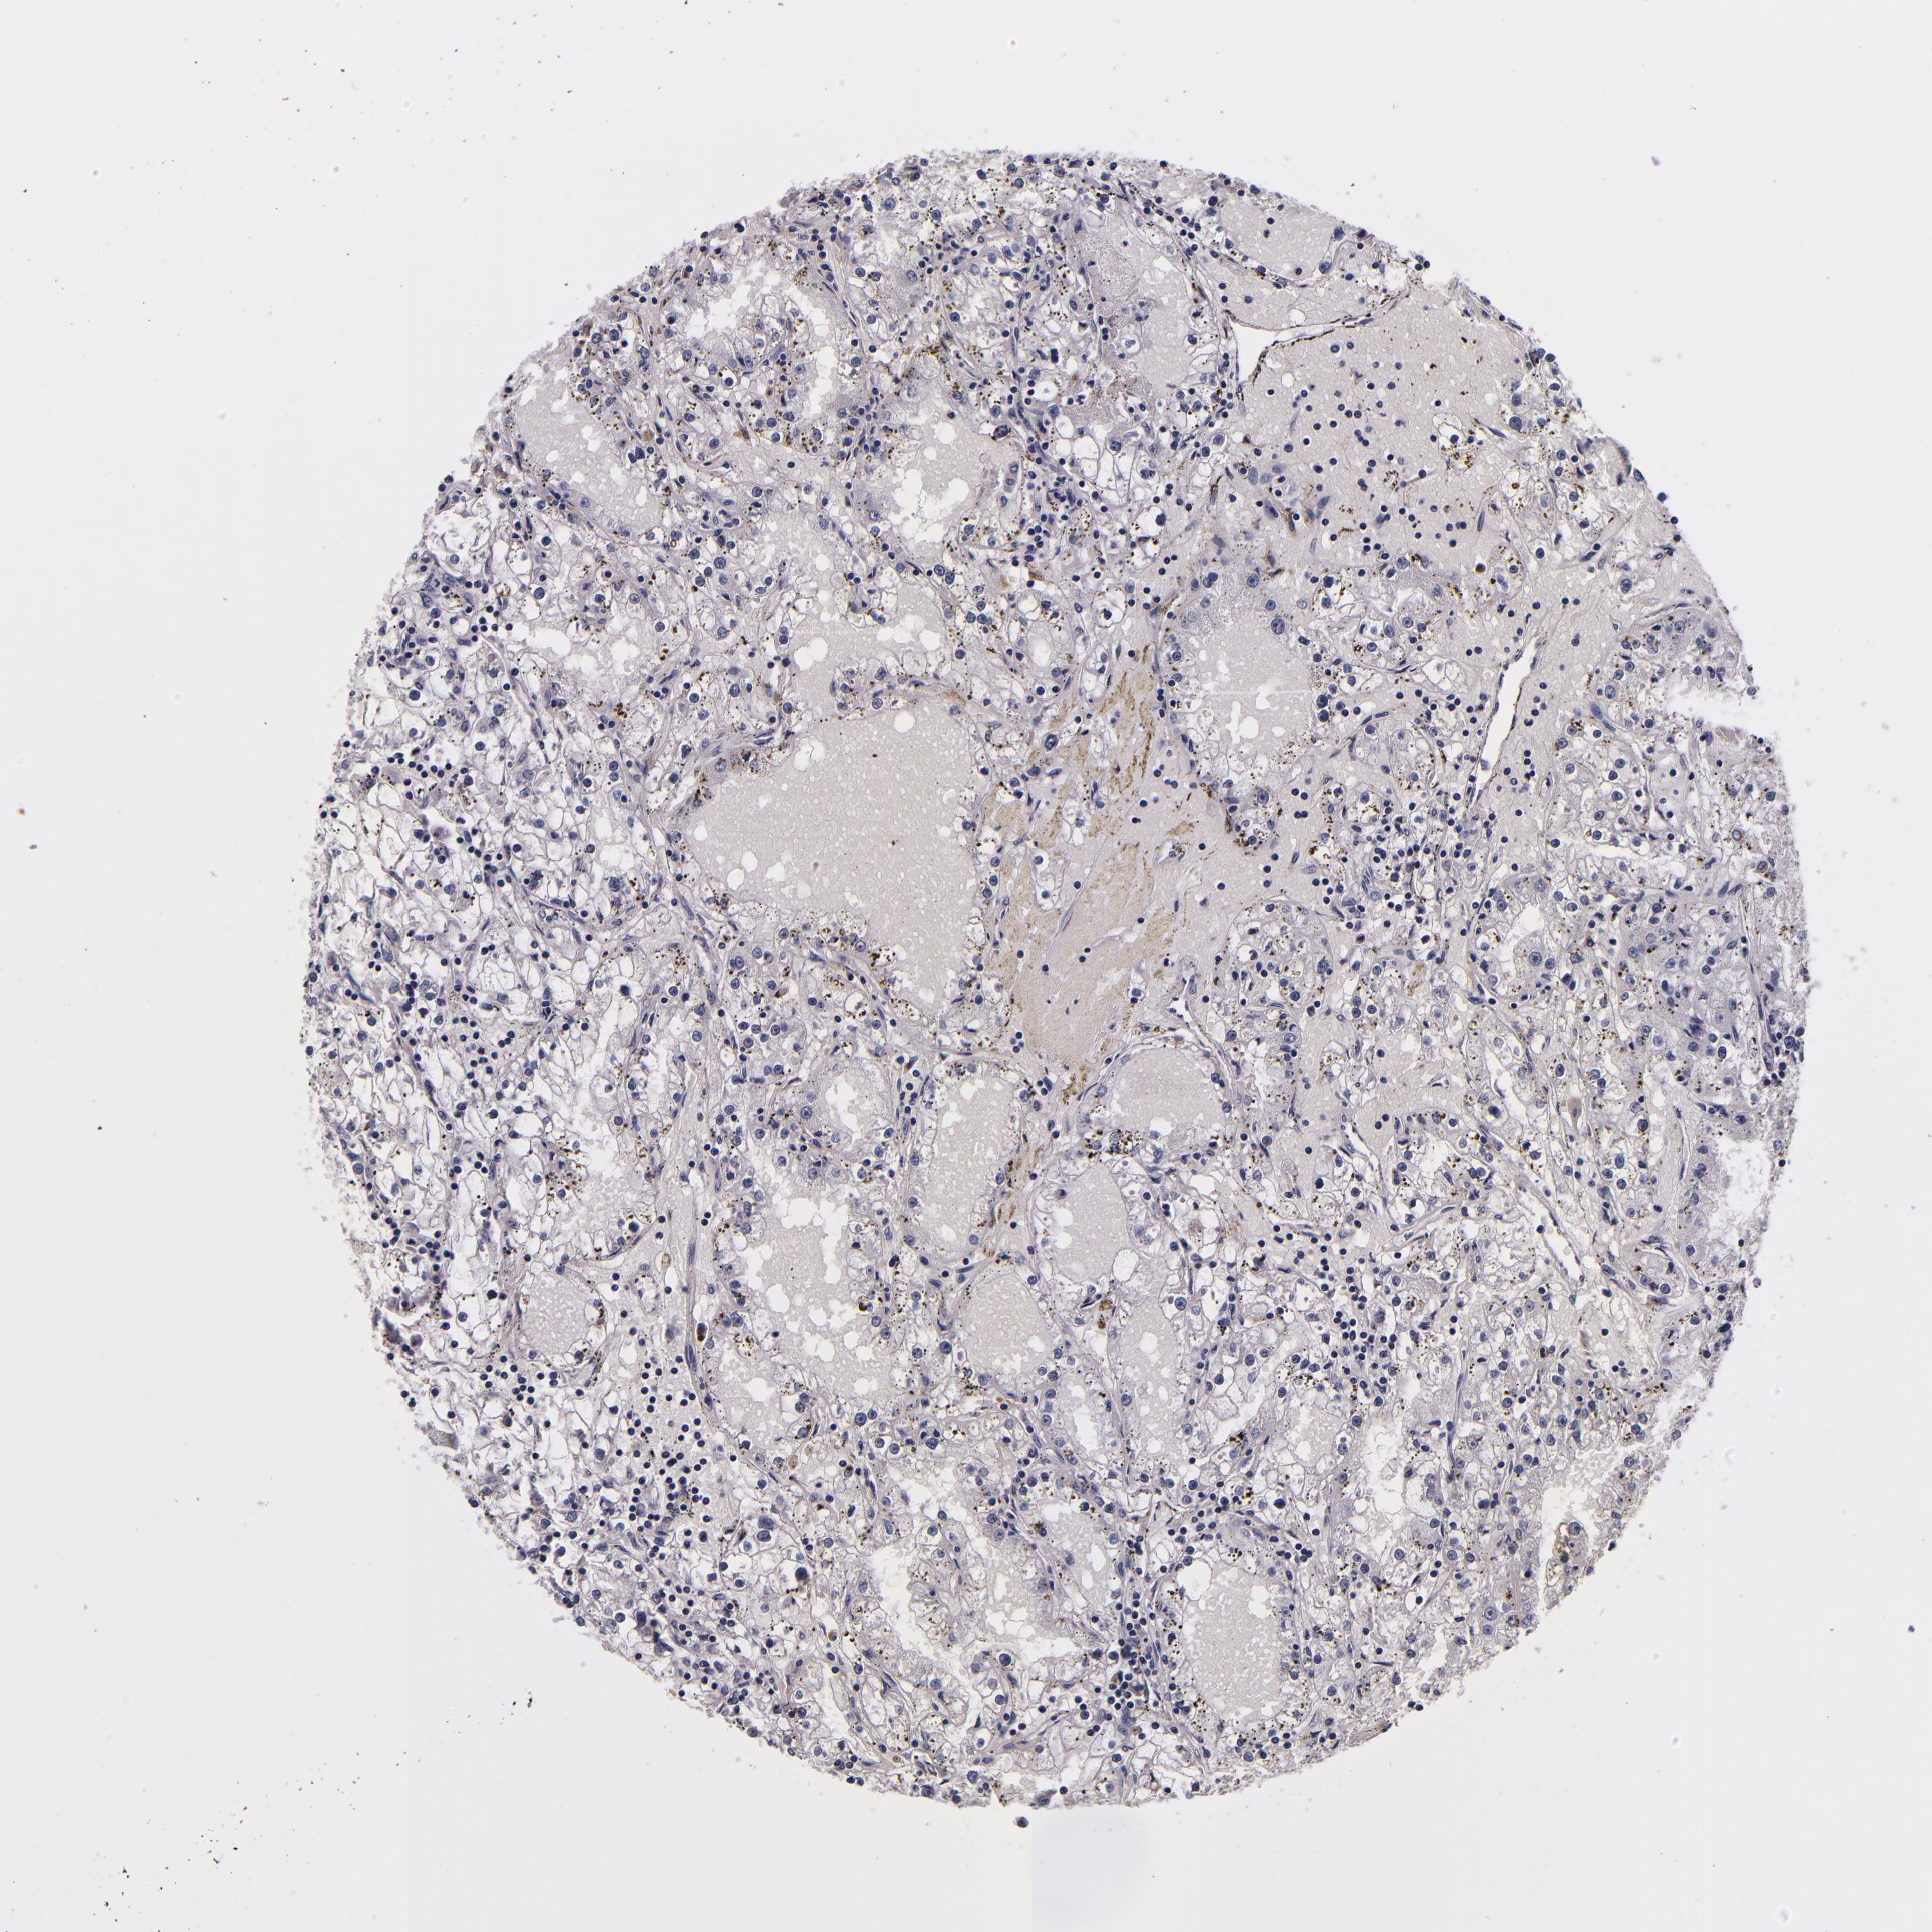

FBN1 is not prognostic in Kidney Renal Clear Cell Carcinoma (TCGA)

Best expression cut offi

When clicking on this number, the vertical dashed line indicating cut-off, the interactive survival plot, and the Kaplan-Meier curve will be adjusted to show results based on the best expression cut-off.

: 3.9

TCGA RNA samplesi

RNA-seq data is reported as average FPKM (number Fragments Per Kilobase of exon per Million reads), generated by the The Cancer Genome Atlas (TCGA) .

Normal distribution across the dataset is visualized with box plots, shown as median and 25th and 75th percentiles. Points are displayed as outliers if they are above or below 1.5 times the interquartile range. FPKM values of the individual samples are presented next to the box plot.

Average pTPM 7.0

Number of samples 521